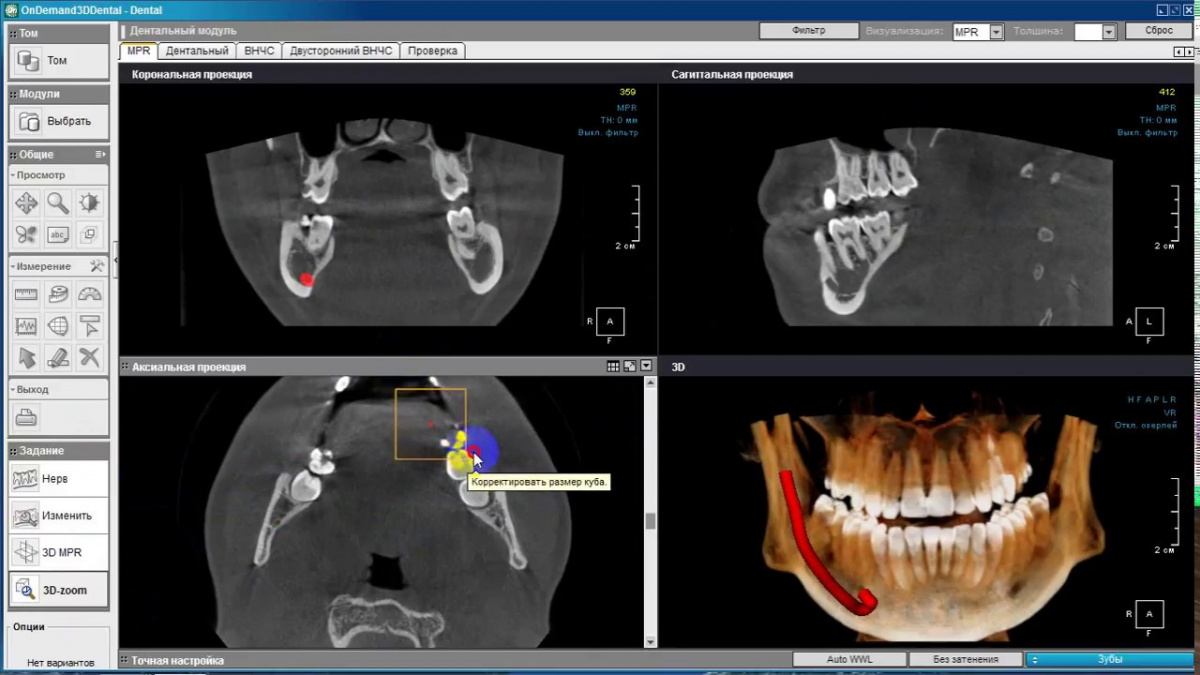

Немаловажным, а может главным вопросом, является универсальность программы-просмотровщика, в которой будут работать врачи-стоматологи. У Papaya 3D есть два варианта программ: Triana и OnDemand3D. Оба просмотровщика обладают схожим интерфейсом и имеют самые важные опции, а именно:

• режим MPR (многоплоскостная реконструкция). Именно здесь выстраивается интересующий участок челюсти или зуба для анализа.

• панорамный реформат. Возможность постройки классической и сегментарной панорамы позволяет продемонстрировать план лечения пациенту, а также оценить расположение анатомических структур на боковых кросс-секциях.

• модуль дентальной имплантации. Возможность виртуальной установки дентального имплантата с анализом окружающей костной ткани. В библиотеке представлен широкий спектр имплантологических систем с индивидуальной прорисовкой имплантата.

• выделение нижнечелюстного канала позволяет продемонстрировать расположение важного анатомического образования и определить зону безопасности при проведении лечения.

• функции плотности, линейных измерений и угла – необходимы для получения полноценной информации для последующего лечения.

• 3D режим – показывает трехмерную модель челюсти с целью определения аномалий, деформация, а также визуализации виртуальных имплантатов.